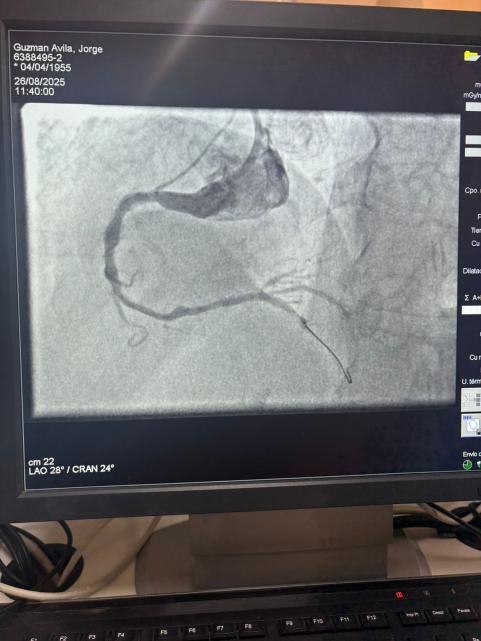

Мы гордимся тем, что поделились замечательным случаем из больницы Sótero del Río, Чили, где доктор Мартин Вальдебенито успешно вылечил сильно кальцинированное поражение в правой коронарной артерии (первая кривая), используя нашу систему катетера с расширенным баллоном IVL.

Процедура достигла выдающихся результатов, при этом кальцинированная область эффективно треснулась и поток сосудов восстановился. Это является еще одной вехой в расширении глобального доступа к передовым решениям для сложной коронарной кальцификации.

Сравнение между предварительными и послепроцедурными ангиографическими изображениями ясно демонстрирует значительное клиническое влияние нашей технологии IVL.